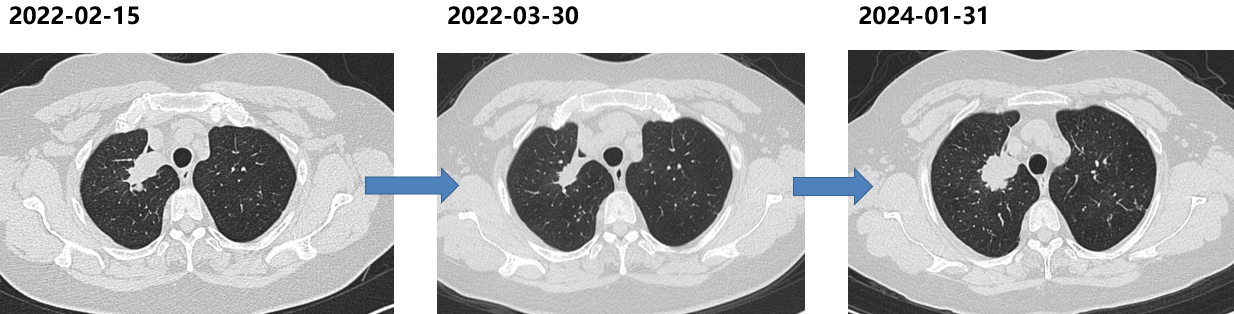

二线治疗(2022-02至2024-01)

诱导期:PD-1单抗+贝伐珠单抗+培美曲塞+卡铂,共6周期。

维持期:PD-1单抗+贝伐珠单抗+培美曲塞。

PFS:23个月。

胸部CT(2024-01-31):肺部病灶进展。

三次活检病理:肺腺癌。

基因检测:EGFR 19del突变。

三线治疗(2024-01至2025-01)

依据:再次活检仍提示腺癌且EGFR 19del阳性,考虑EGFR-TKI再挑战。

方案:

药物:阿美替尼110mg QD。

胸部CT和脑MRI(2025-01-30):肺部病灶进展,右侧脑转移病灶。